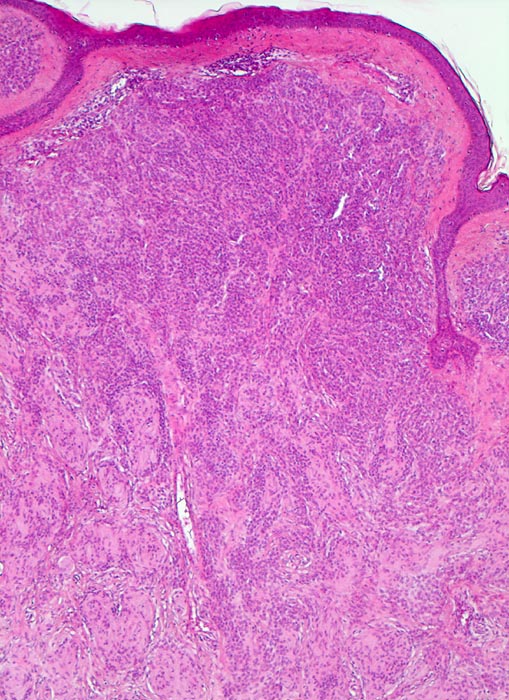

Verlauf: Erworbene Naevi können ein lentiginöses oder ein kongenitales Wachstumsmuster aufweisen (Ausbreitung der Naevuszellen in der tieferen Dermis entlang von Adnexstrukturen). Letzteres bedeutet nicht, dass der Naevus bei Geburt schon bestand. Am Anfang der Entwicklung erworbener Naevi steht die Lentigo simplex ( 5299), welche durch Vermehrung einzeln liegender Melanozyten im Bereich der basalen Epidermis zustande kommt und makroskopisch als scharf begrenzte braune Makula imponiert. Daraus entwickeln sich junktionale Naevi mit Nestern von jeweils drei oder mehr Naevuszellen in der basalen Epidermis ( 5362). Bei Compound Naevi (= dermoepidermaler Naevuszellnaevus) finden sich zusätzlich zu den epidermalen auch intradermal gelegene Naevuszellen oder Nester von Naevuszellen ( 565). Compound Naevi zeigen ein sehr variables makroskopisches Bild von gering erhabenen bis zu polypoiden, gestielten oder verrukösen Läsionen. Die Farbe variiert von braun über grau bis zu hautfarben. Diese Naevi bleiben über Jahre weitgehend unverändert und entwickeln sich schliesslich weiter zu rein dermalen (=corialen) Naevi mit ausschliesslich intradermal gelegenen, oftmals unpigmenierten Naevuszellen, um schliesslich vollständig zu verschwinden.

Kennzeichnend für einen gutartigen Naevuszellnaevus ist dessen Symmetrie und die Ausreifung der intradermalen Naevuszellen von oberflächlich gelegenen grossen, runden, pigmentierten Zellen in grossen Nestern, zu tiefer gelegenen kleineren, runden, nicht pigmentierten, in kleineren Nestern oder einzeln liegenden Zellen und in älteren Läsionen zu spindeligen Zellen mit neuralem Phänotyp mit Verlust der melanozytären Differenzierung (sogenannter Neuronaevus). Gewöhnliche Naevi zeigen keine zytologischen Atypien und die dermale mitotische Aktivität ist minimal.

Die Tumorzellen bilden Nester in der Epidermis und in der Dermis (=dermoepidermaler bzw. compound Naevus).

Die oberflächlichen Naevuszellen zeigen reichlich helles, teils pigmentiertes Zytoplasma und helle ovale Kerne mit kleinen, deutlich erkennbaren Nukleolen. Zur Tiefe hin werden die Naevuszellen kleiner, haben weniger Zytoplasma und dunkle kleine Kerne ohne gut erkennbaren Nucleolus. Die Zellnester werden zur Tiefe hin ebenfalls kleiner (=Ausreifung).

Keine Mitosen, keine Zellatypien.